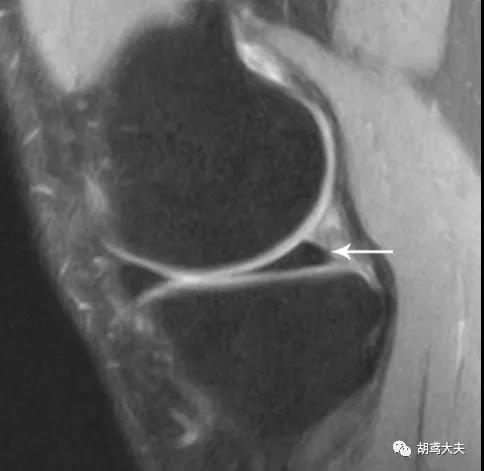

再来看片子,先看正常的:

正常的半月板后角如图(箭头所指黑色三角形)